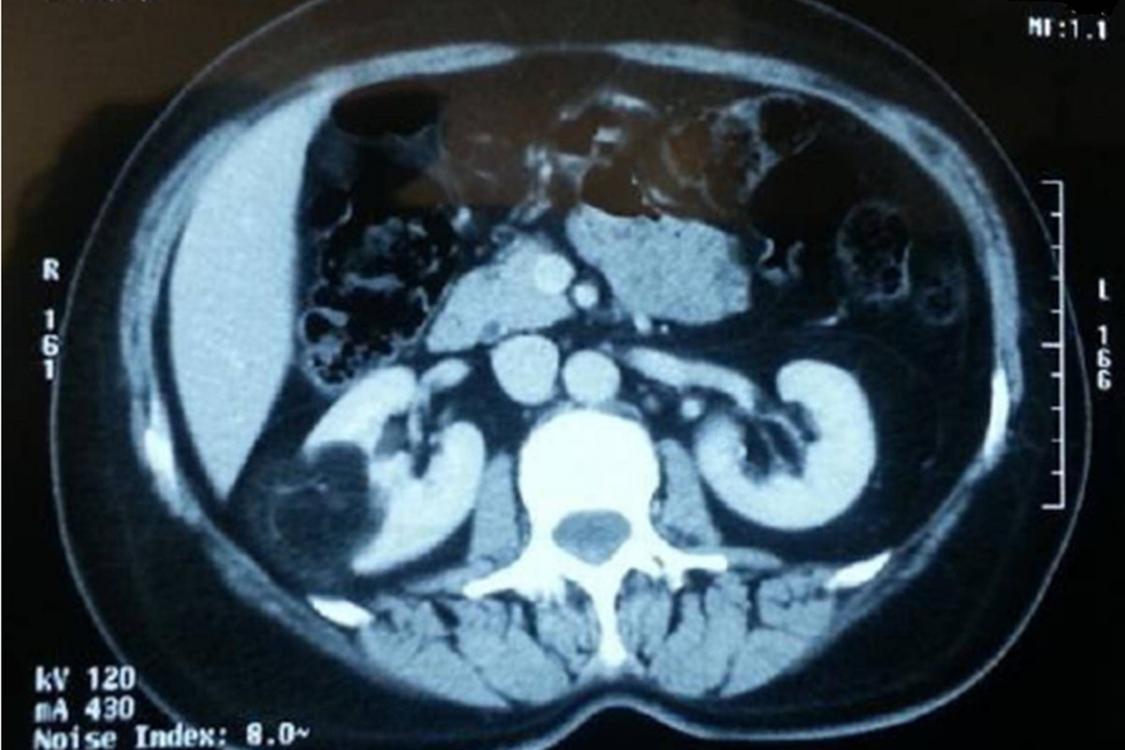

The study evaluated abdominal CT scans performed on adult patients and observed that a substantial number of cases presented with simple renal cysts — fluid-filled sacs located within the kidneys. These cysts were not associated with any urological symptoms or underlying kidney conditions.

- The majority of cysts were classified as Bosniak category I, indicating simple cysts with benign characteristics.